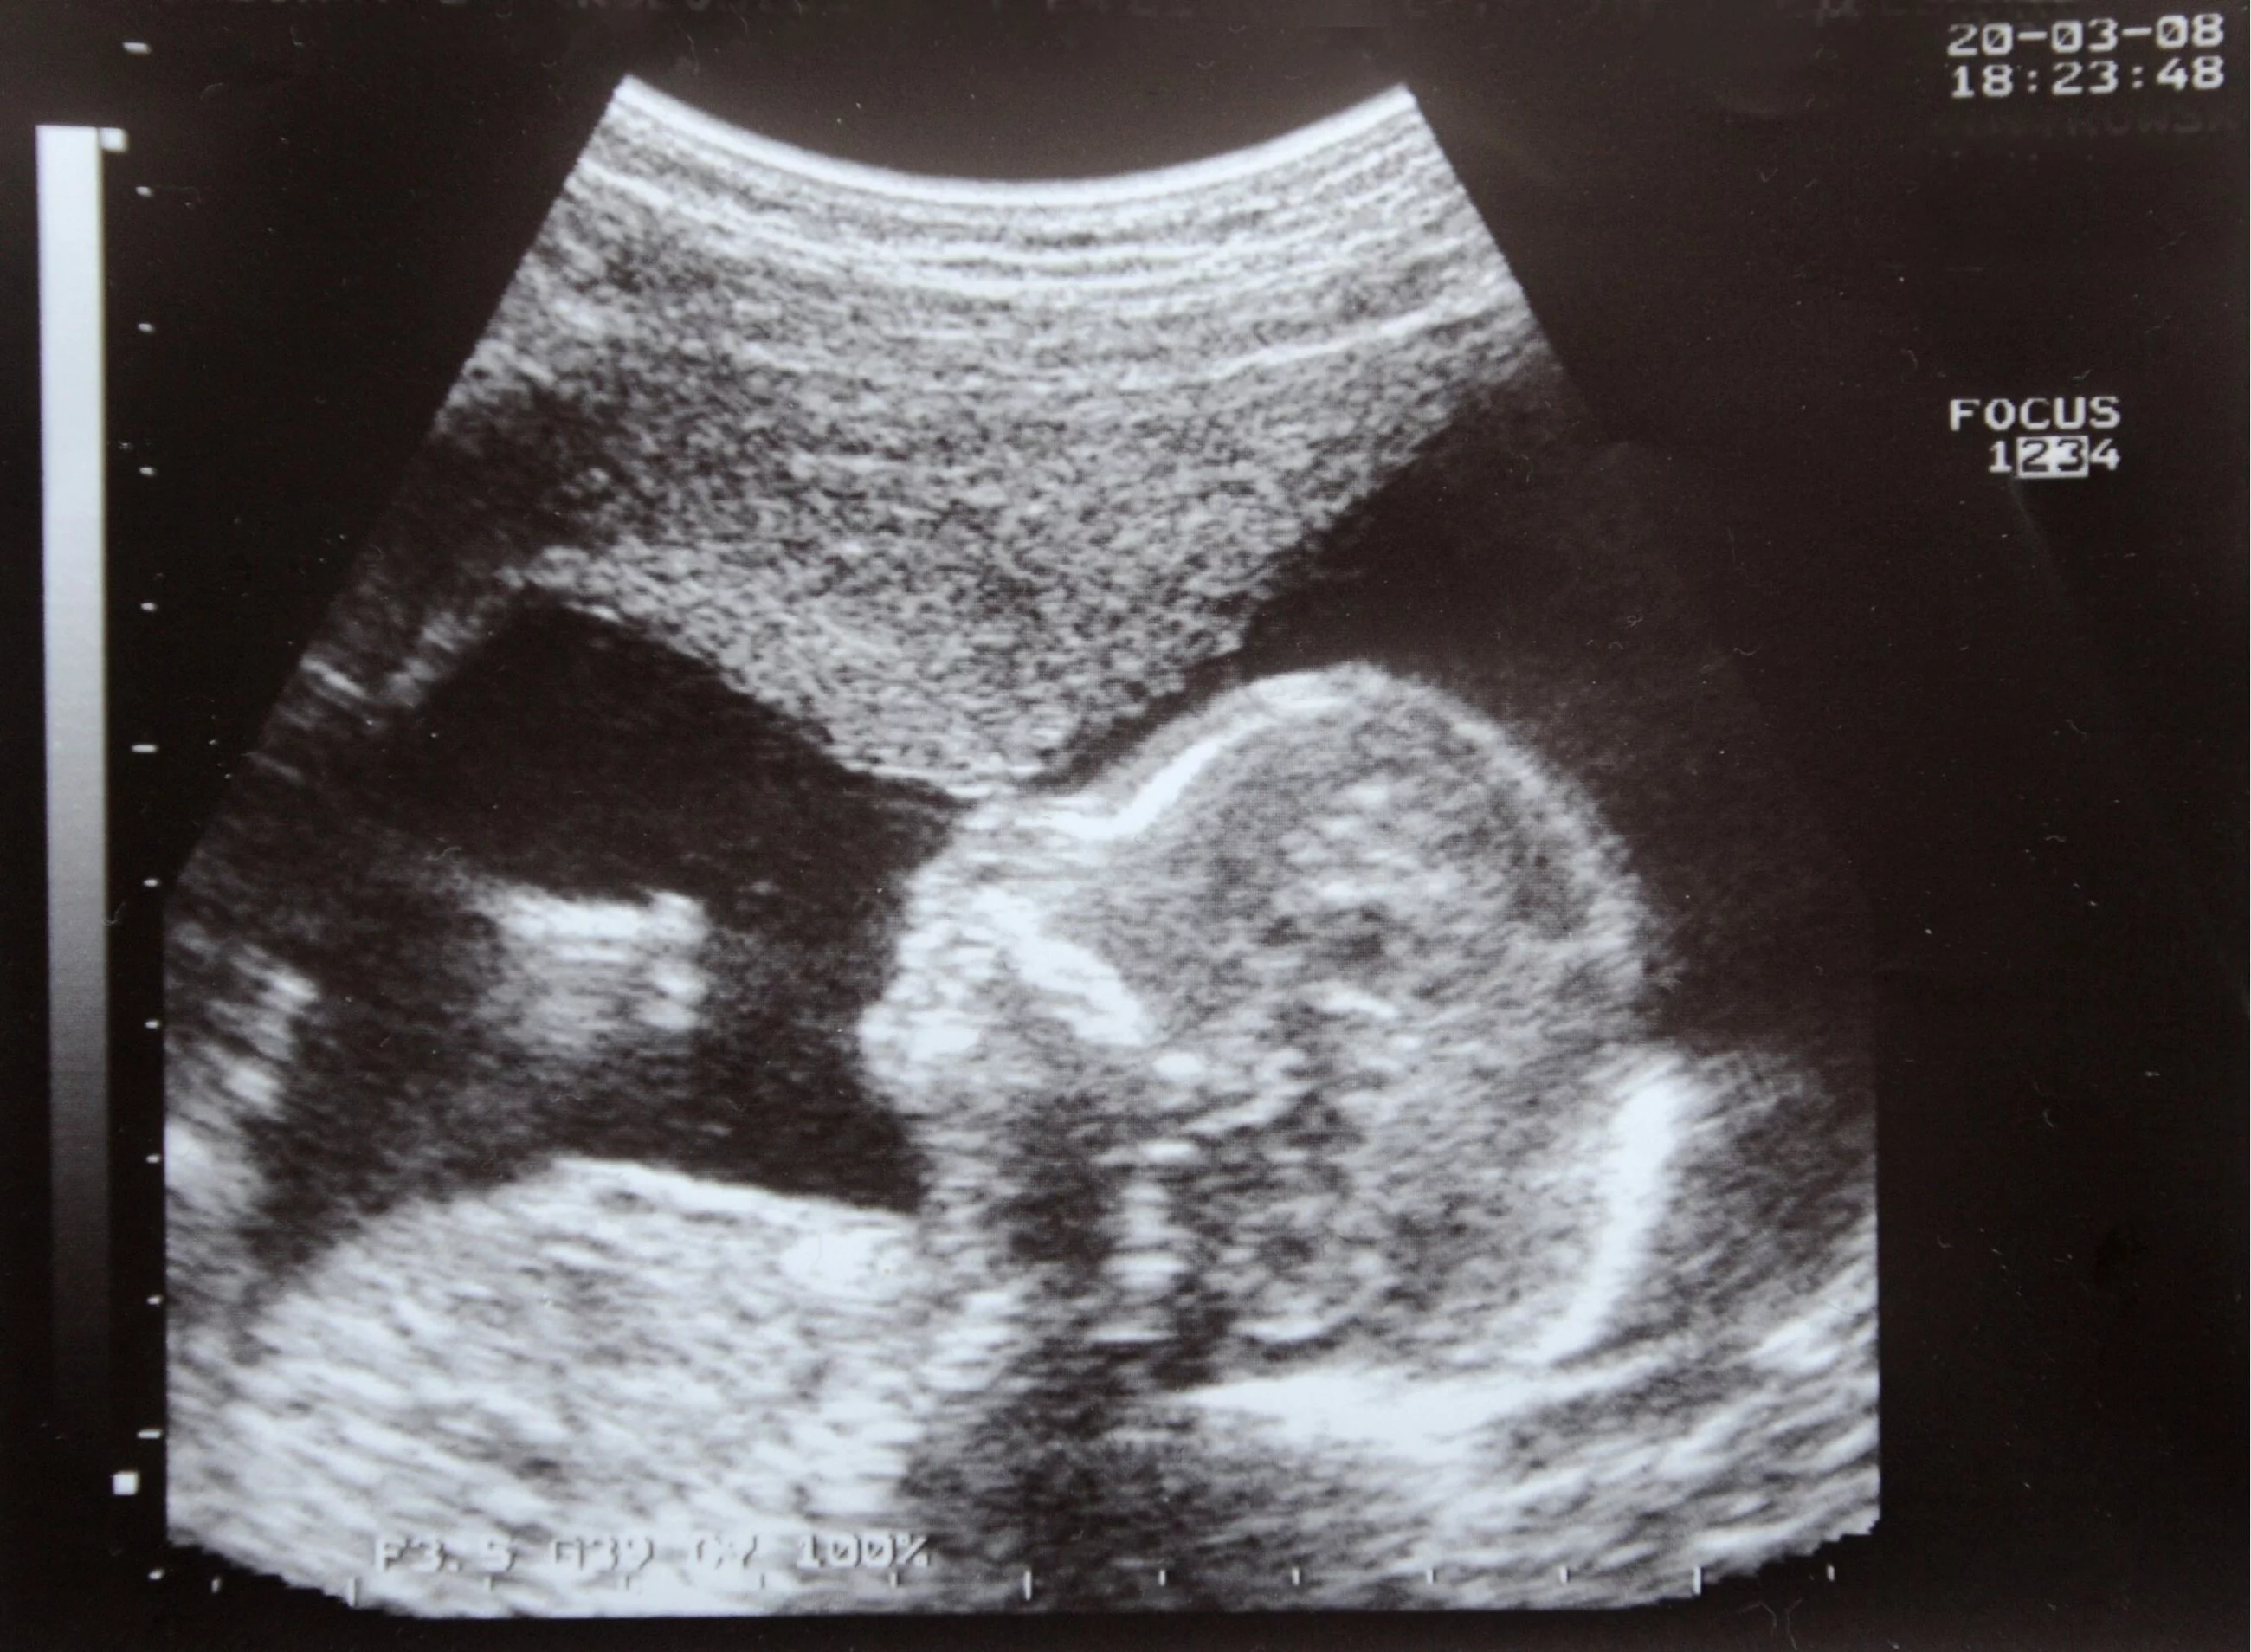

W Narodowym Systemie Zdrowia płeć dziecka zwykle nie jest ujawniana przed 18. tygodniem ciąży, ale prywatne nieinwazyjne testy prenatalne mogą ustalić płeć już w 7. tygodniu, co – według krytyków – może umożliwiać decyzje o aborcji ze względu na płeć.